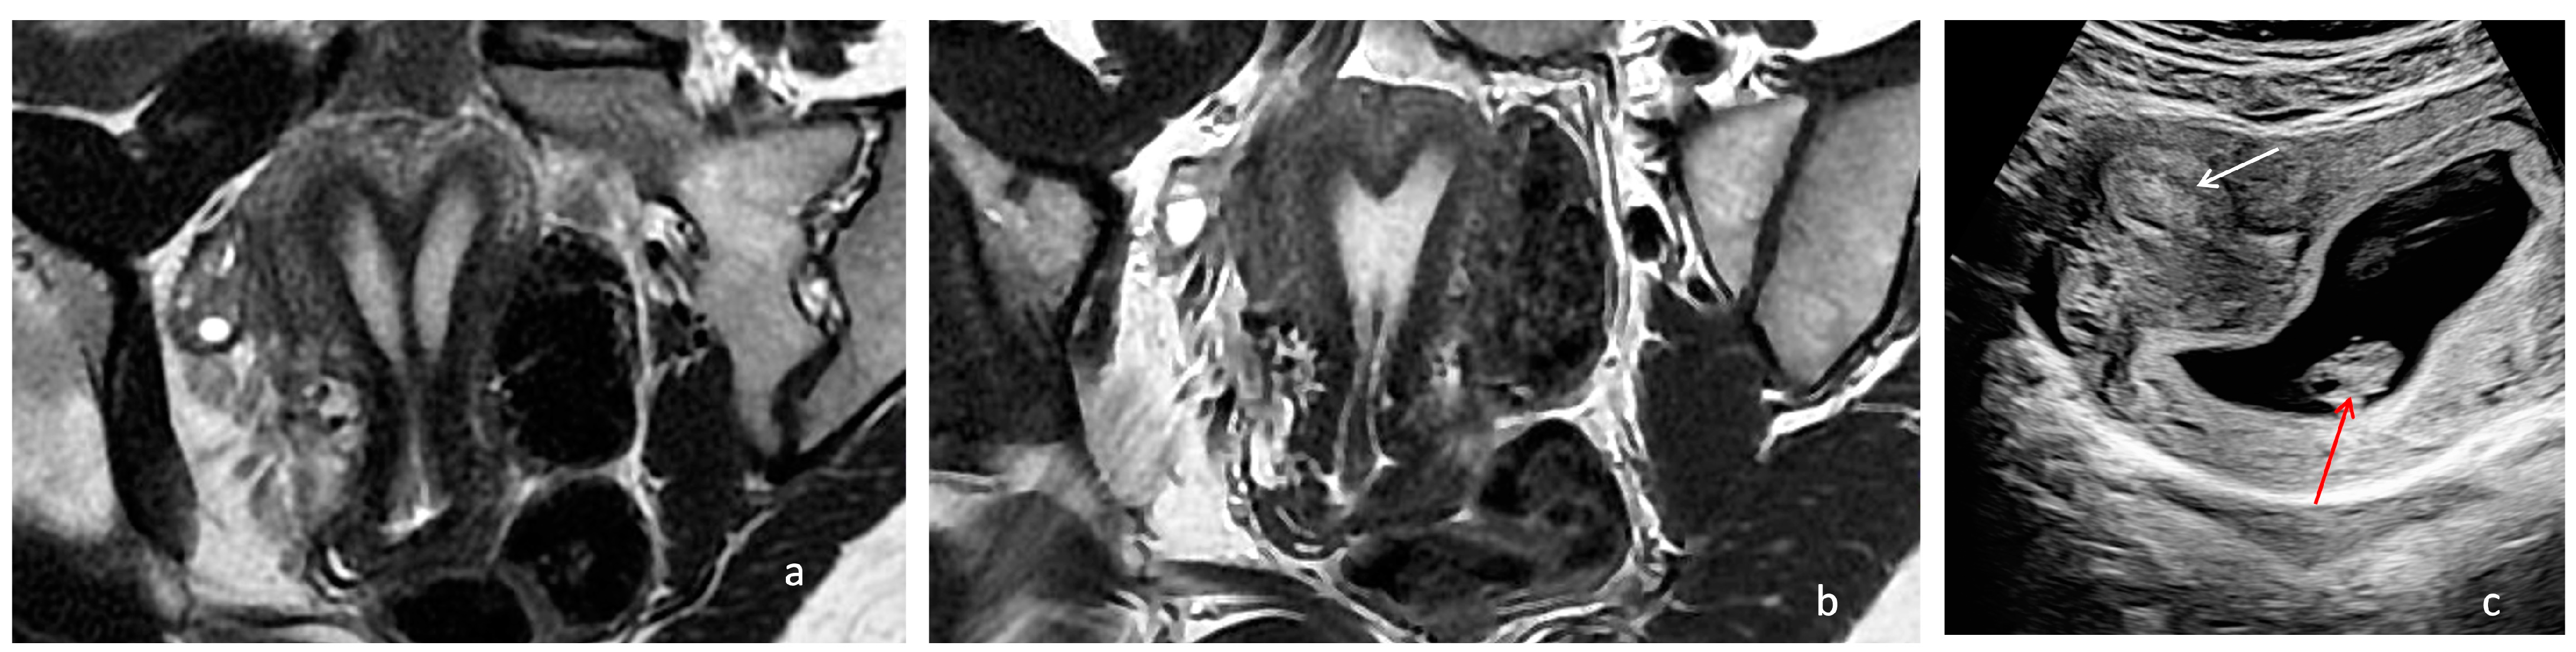

The MRI confirmed the presence of a Müllerian anomaly (Figure 4a). Like in the first two cases, hysteroscopic removal of the uterine septum up to the isthmic level, sparing the two cervices, and resection of the longitudinal vaginal septum were performed. A single uterine cavity was obtained with a slightly arcuate appearance (Figure 4b). The patient was discharged on the same day with a two-month estrogen pill regimen to prevent the occurrence of uterine synechiae.

Figure 4. Preoperative and postoperative examination of case 3. (a) Preoperative MRI T2, WI, showing the two uterine cavities separated by a complete uterine septum and cervix duplication. (b) Postoperative MRI depicting a single uterine cavity with a slightly arcuate appearance. (c) Two-dimensional ultrasonography in which the embryo can be seen (red arrow) and the decidualized region is towards the right uterine horn (white arrow).

The patient came for a check-up after three months, but due to secondary amenorrhea, the control hysterosalpingography was not performed. The patient became pregnant spontaneously, and during the pregnancy confirmation ultrasound, a decidualized region could be observed towards the right uterine horn, lateral to the area of origin of the base of the septum (Figure 4b). The pregnancy is ongoing at the time of manuscript submission and has been uncomplicated up to the third trimester of pregnancy.